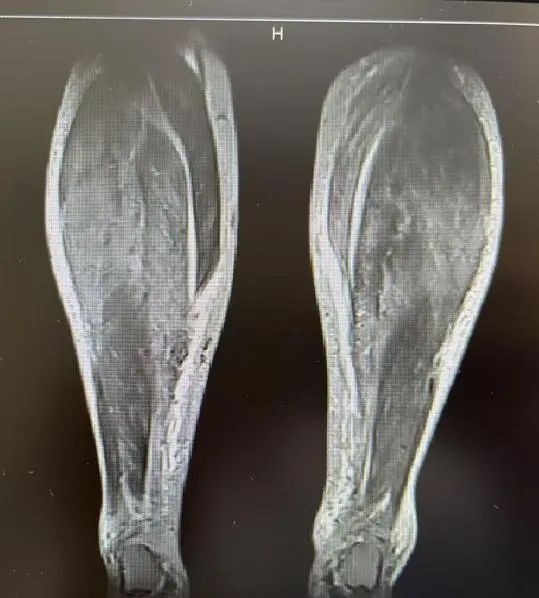

接诊时,李女士的情景很是危险。风湿免疫科主任庄宇、张雪珍副主任医师经详备问诊和针对性查验后,马上捕捉到重要信息:肌肉无力致行走艰难、吞咽艰难激发呛咳、呼吸艰难领导肺部受累;血液检测中,肌酸激酶(CK)高达 14314 U/L,远超浅显值百倍;勾通特异性抗体(抗 SRP 抗体)阳性等成果,会诊指向了不吉的免疫介导坏死性肌病(IMNM)——这是一种进展迅猛、可累及呼吸、吞咽及心肌的危重自己免疫性疾病。

李女士所患的免疫介导坏死性肌病(IMNM),属于特发性炎性肌病的亚型,是一种冷漠的自己免疫性肌肉疾病,会因不同类型抗体而有不同的临床推崇,主要以亚急性近端肢体肌无力和血清肌酸激酶(CK)显赫升高为特征,肌肉无力进展迅猛且严重,常快速涉及算作、吞咽及呼吸功能。其中枢计制是免疫系统很是报复肌肉组织,导致肌肉毁伤。